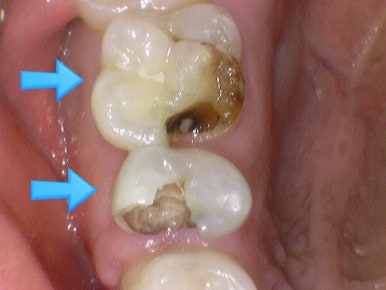

신경치료하고 크라운 안 한 치아->파절

신경치료하고 크라운 안 한 치아->파절이 흔합니다. 위 사진처럼 깎아서 크라운을 할 부위가 거의 없으면 잇몸위에다 크라운을 붙일 순 없겠죠. 발치가능성이 아주 커집니다.